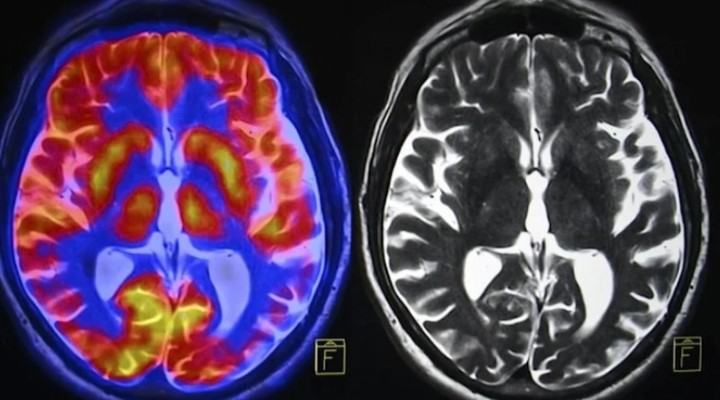

?nsanlar?n beyni küçülüyor!

Bilim insanlar? insan beyninin son 50 y?lda küçüldü?ünü aç?klarken, baz? uyar?larda bulundu.

Beyin ?çin G?da Vakf?’n?n bir etkinli?inde konu?an Crawford, kötü beslenme ve al??kanl?klar sebebiyle beynin kütlesinde ve IQ seviyelerinde ciddi bir kay?p oldu?unu duyurdu. Crawford, “IQ seviyeleri 1970’den beri dü?üyor ve bu gerçekten komik de?il. Çünkü e?er bu durum devam ederse homo sapiens türünün sonu gelebilir” dedi.

Beyin sa?l??? için beslenmenin öneminin kaç?r?ld???na dikkat çeken Crawford, beyin sa?l??? için ya?l? bal?klar?n daha s?k tüketilmesi gerekti?inin de alt?n? çizdi. Profesör Crawford, “Modern insan beyni, erken dönem atalar?m?z?n beyinlerine göre yüzde 17 oran?nda daha  küçük” dedi. Çocuklar?n ve onlar?n çocuklar?n?n da gelece?inin risk alt?nda oldu?unu belirten Crawford, hamilelerin ve çocuk sahibi kad?nlar?n da çocuklar?n emzirilmesi için omega-3 deposu bal?klar? tercih etmesi gerekti?ini söyledi.